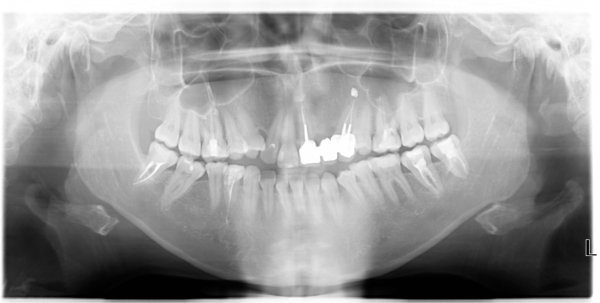

2 дня назад была у стоматолога, у меня на 6-ке внизу стояла коронка. Она спала, там была половина зуба и остальное пломба, когда коронка спала, то отломалось еще пол той стороны зуба.

У стоматолога была, снимок сделала, корни сказал хорошие, удалять не надо, как он посмотрел зуб, то отпала пломба, держаться не на чем было, сказал ставить вкладку и на неё коронку. Начал подготавливать зуб, каналы прочистил, остаток зуба сточил, сделал слепок для вкладки и назначил следующий визит через неделю.

В данном зубе имеются три очевидные проблемы:

• имеется воспаление на верхушке корня (периодонтит), который подлежит лечению перед установкой вкладки;

• наблюдаются изменения по бифуркации;

• начальная стадия кариеса корня.

Все симптомы говорят о том, что необходимо сменить доктора и более внимательно и качественно отнестись к лечению данного зуба. Необходим детальный развернутый снимок с разных ракурсов. Необходимо сейчас обратиться к врачу и лечить обострение периодонтита и только потом заниматься протезированием. В противном случае данный зуб вы можете потерять.